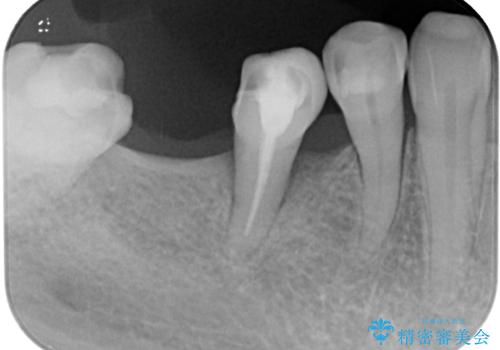

歯が割れて抜歯になってしまったとのことと、ブリッジの土台となる手前の歯は既に神経が取り除かれていて、こちらも破折するリスクが高いことから、咬合力に抵抗できるよう、インプラントによる補綴治療を行うこととしました。

インプラント埋入時に植立具合の安定性を測定したところ、十分な数値が得られたため、速やかに仮歯を装着して咬合回復をさせることができました。